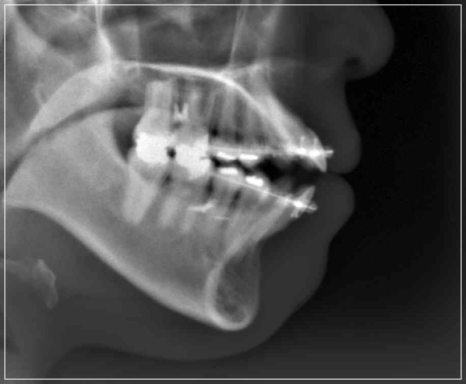

입이 안 다물어지는 문제를 해결한 모습

태어날때 부터 생긴 문제로 인한

개방교합은 보통 치아 교정을 통해

해결하면 된다고 생각하시는 분들이 많은데,

만일 턱관절 질환으로 인해 생긴 경우

잘 모르고 치아 교정부터 진행하게 되면

턱이 불안정한 상태에서 치아를

움직이게 되기 때문에 오히려 질환을

악화시키거나 무리한 치아 이동으로 인해

개방교합이 다시 생겨나는 등 문제가

발생할 수 있어서 주의가 필요합니다.